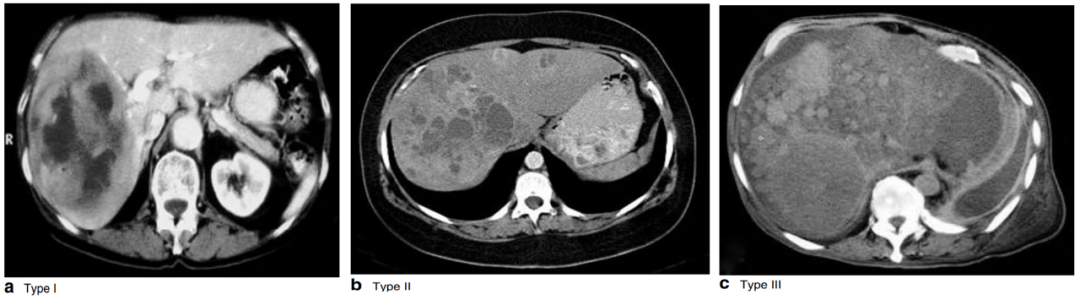

临床中,高达32%~77%的pNENs患者诊断时发生肝转移,肝转移往往是肿瘤进展最快的转移部位,为pNENs最重要的独立预后因素。A.Frilling等人将NENs肝转移分为3型:

• 简单型(Ⅰ型):转移瘤局限于一叶或相邻两段,可行标准的解剖性切除,约占20%~25%。

• 复杂型(Ⅱ型):一叶为主,伴周围较小的、散在分布的卫星灶,但仍可外科处理,约占10%~15%。

• 弥漫型(Ⅲ型):为两叶弥漫分布的转移瘤,通常无法手术干预,约占60%~70%。

△A.Frilling等提出的神经内分泌瘤肝转移分型